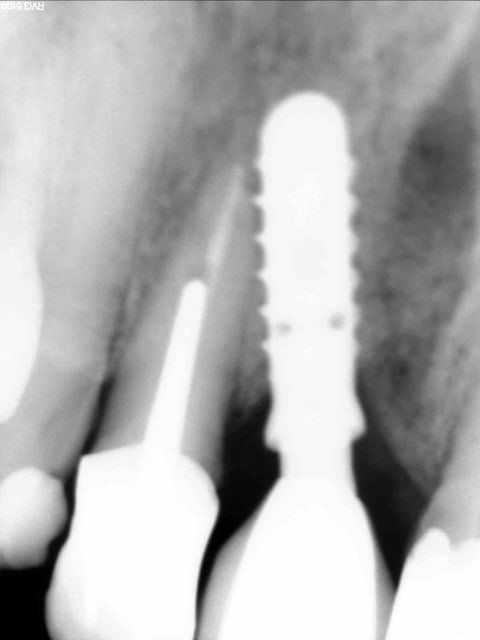

Céramik comme promis Ma réponse en image 2ans après

1 Pano du cas

2 Pano qui a déclenché tous ces gentils commentaires

3 Rx le jour de la POSE de la dent

4 La dent le jour de la pose

5 Pano aujourd'hui (le secteur 4 fichu???)

6 Rx aujourd'hui

7 La dent 2ans après

Vos avis!

C'est un implant Léone